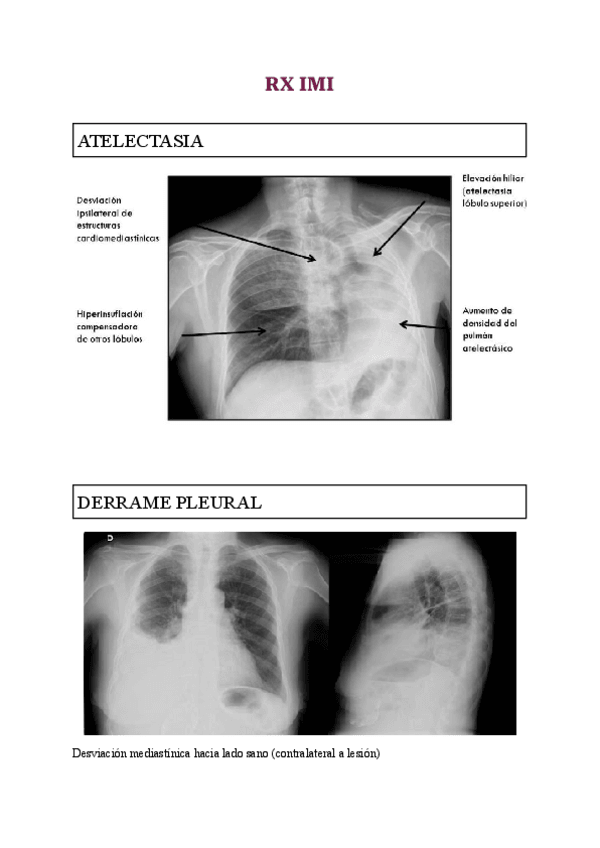

He publicado nuevos apuntes de 2º Introducción a la medicina interna y propedéutica clínica: RECOPILACION-RX-IMI-1-y-2-cuatri.pdf